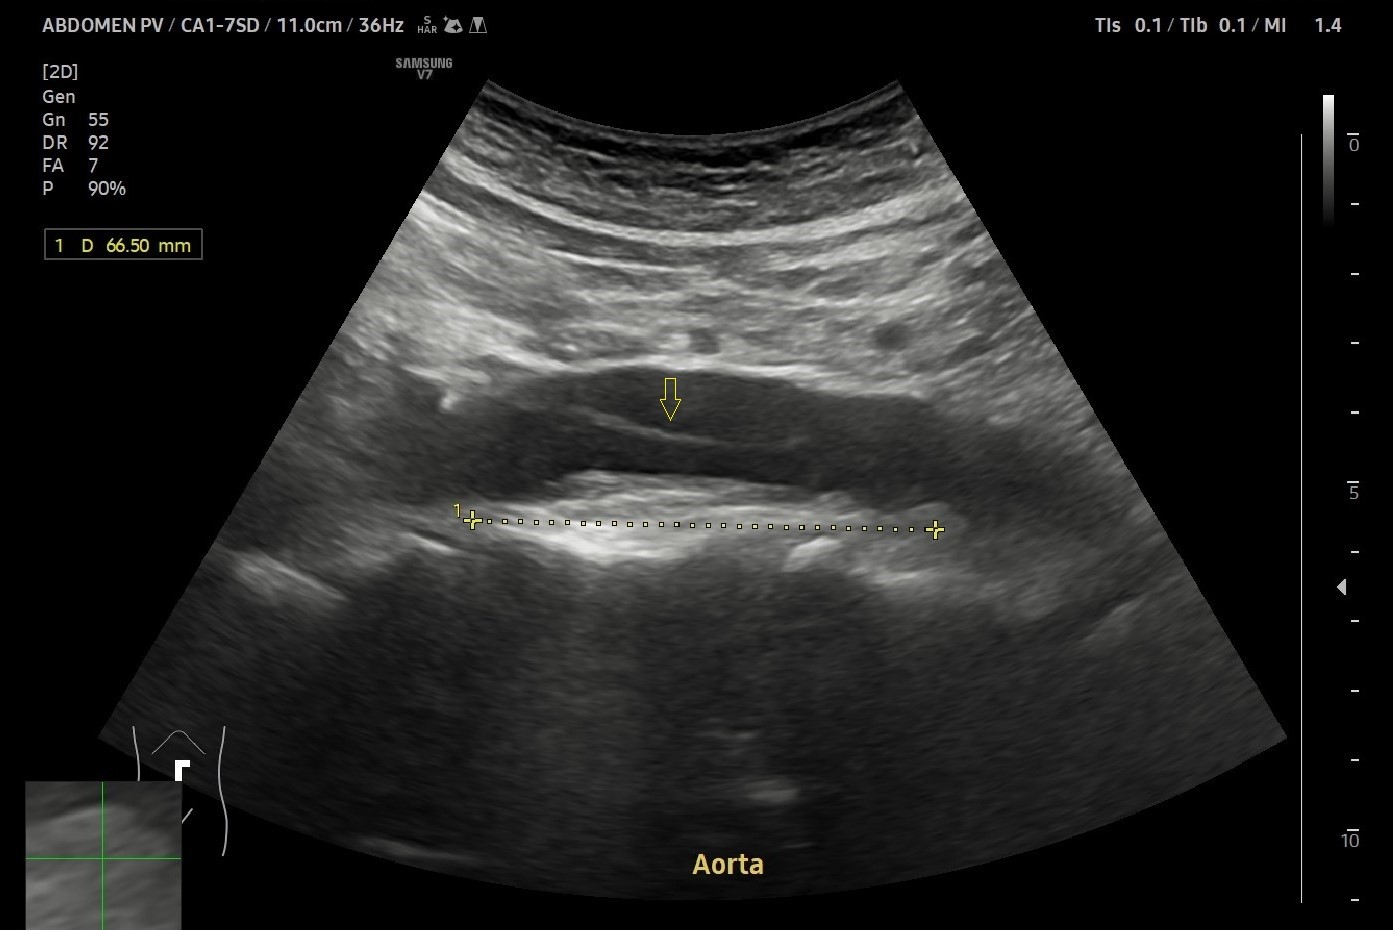

Fig. 4. An example of chronic dissection of the infrarenal abdominal aorta in the longitudinal plane in a 70-year-old patient. The dissection corresponds to a thin hyperechoic line in the aortic lumen.

Recognizing double aorta artifact is essential because it can mimic more serious conditions such as aortic dissection and abdominal aortic aneurysm (AAA) (Fig. 4-6)